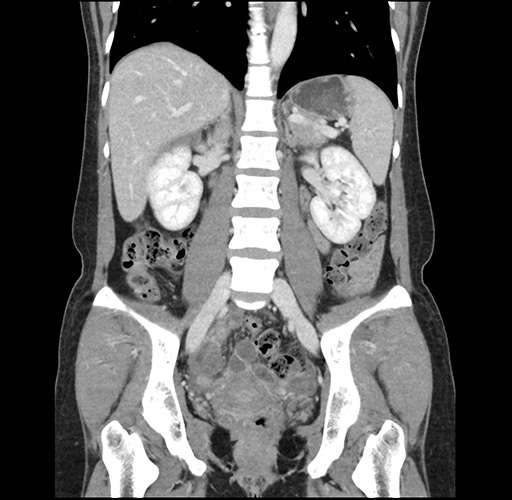

Imaging Analysis

Look through the patient's CT scan to identify any areas of concern for the necessary procedure.

Based on your CT findings, which issue(s) would give reason for "planned slowing down moment(s)" in this case?